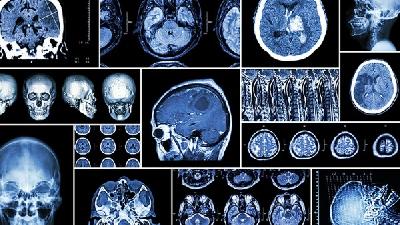

脑萎缩的可能原因